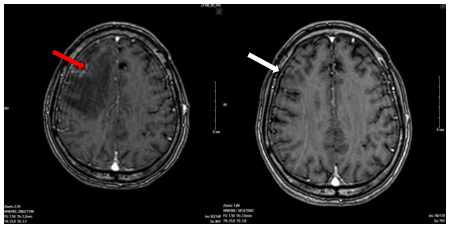

Hình 6.

Hình ảnh phim chụp cộng hưởng từ não ngày 12 tháng 07 năm 2025 (mũi tên trắng) so với ngày 25 tháng 03 năm 2025(mũi tên đỏ) cũng thể hiện kích thước khối u đã giảm đáng kể so với phim chụp cũ.